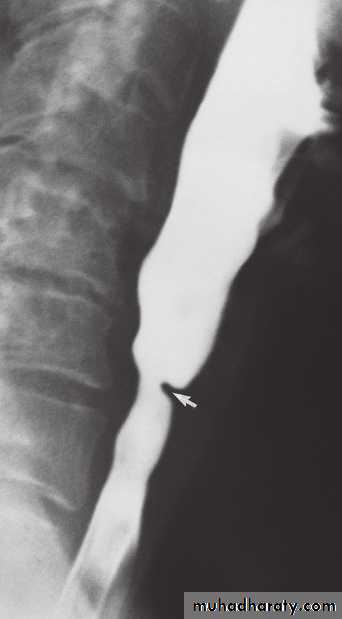

Stricture

Benign vs. malignant Causes Specific locationContrast study EUS CT